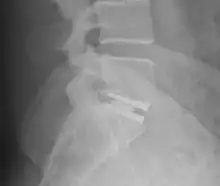

X-ray of interbody fusion cage in L5S1 vertebrae.